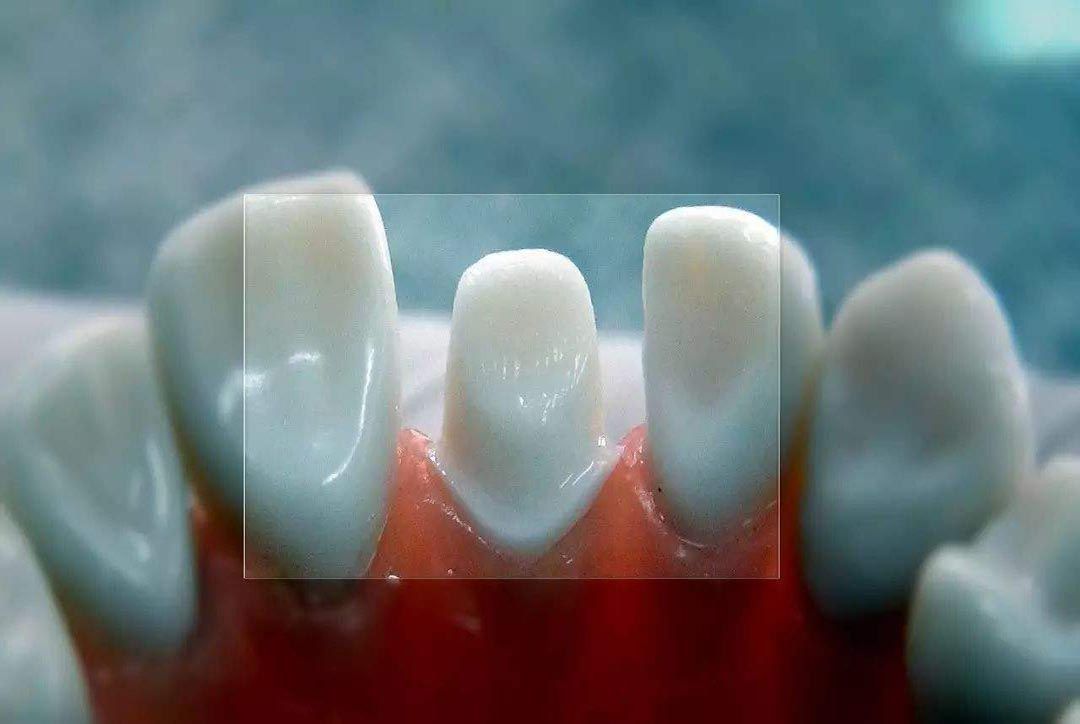

当然多生齿还分为两种,第一种就是萌出口腔的多生齿,这种的话肉眼是可以看到的;还有一种就是埋伏性多生齿,就是埋伏在颌骨中没有冒出头的多生齿。这种多生齿需要在X光的检查下才能看出来,所以这种多生齿处理起来也是相当麻烦,处理的费用也是第一种的五倍左右。那么家长就有可能有这样一种疑问了,宝宝毕竟是要换牙的,可不可以不用处理呢?